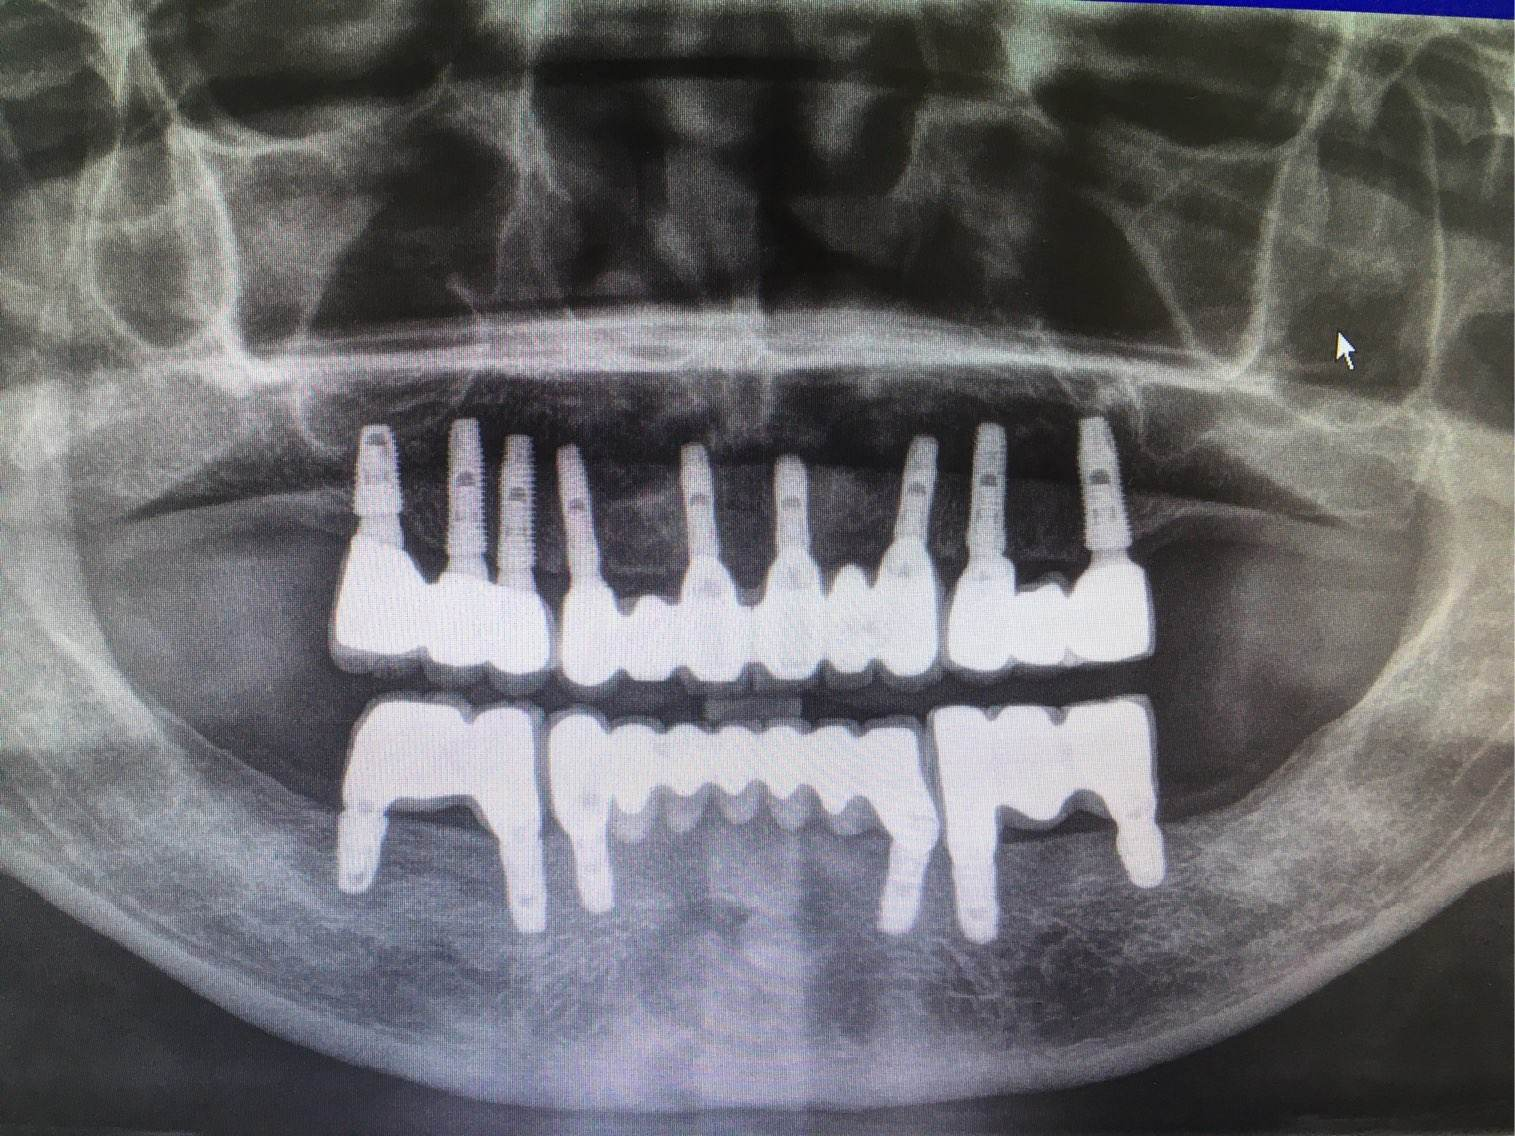

3、種植修復(fù)

適用于:各種多顆牙、半口牙甚至全口牙齒的缺失。

優(yōu)點:恢復(fù)咀嚼功能最多的修復(fù)方式,屬于固定修復(fù),不能自行取下。

缺點:費(fèi)用較高,修復(fù)周期較長,有些還需要植骨。修復(fù)周期從拔牙算起得半年以上的時間。